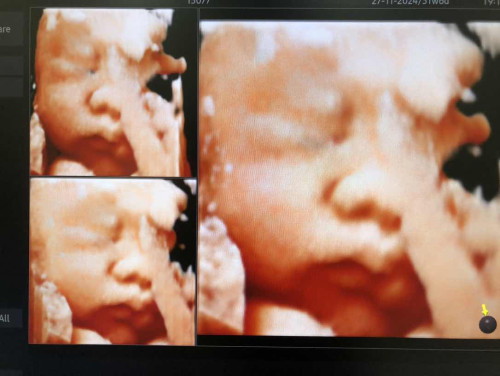

บ้านนี้31w6d นน1888 น้ำหนักน้อยเกินหรืออยู่ในระยะโอเคค่ะ

บ้านนี้กังวนกลัวน้องตัวเล็ก มีแม่ๆบ้านไหนน้อยกว่านี้มั้ยคะ

บ้านนี้ซาวด์ตอน 32+5 ได้ 1880 หมอบอกกำลังดีค่ะ